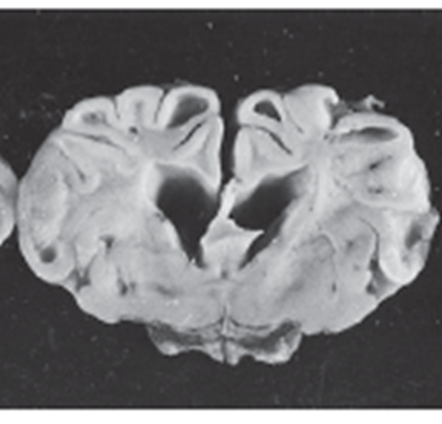

What pathology is shown in this image?

Polyneuritis equi (image)